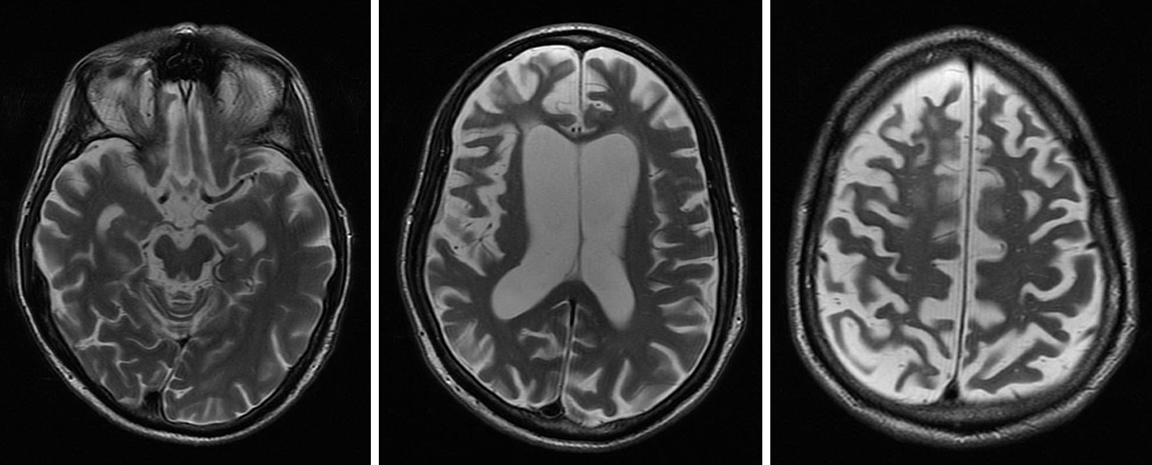

Các nhà nghiên cứu đang xem xét liệu việc chụp cắt lớp phát xạ positron (PET) và chụp cắt lớp vi tính phát xạ đơn photon (SPECT) có thể phát hiện ra những thay đổi trong não phù hợp với bệnh thoái hóa vỏ não-hạch nền hay không. Tuy nhiên, cần phải thực hiện nhiều nghiên cứu hơn trong lĩnh vực này.